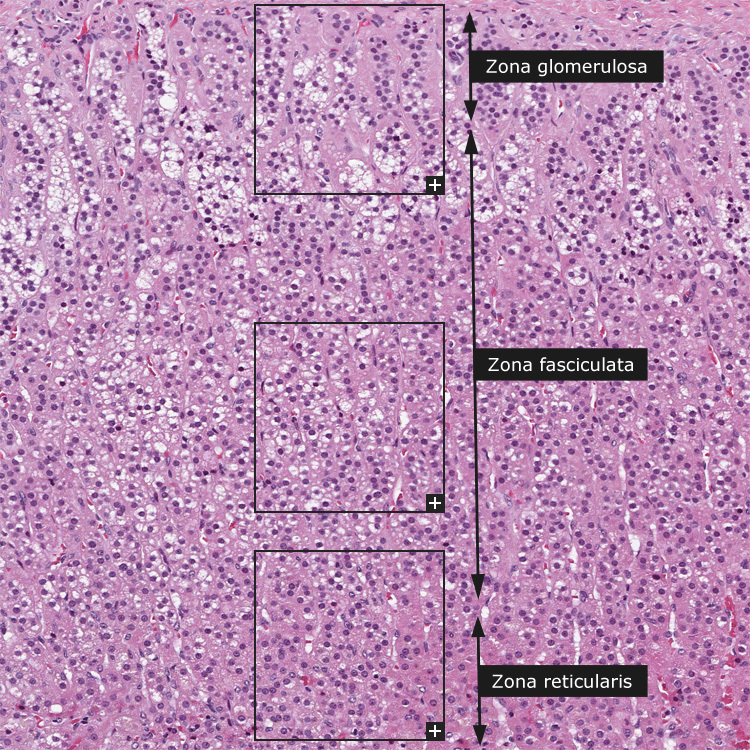

Endocrine system: Adrenal Gland

Epinephrine and Norepinephrine, and an outer region (adrenal cortex) secreting corticosteroids.